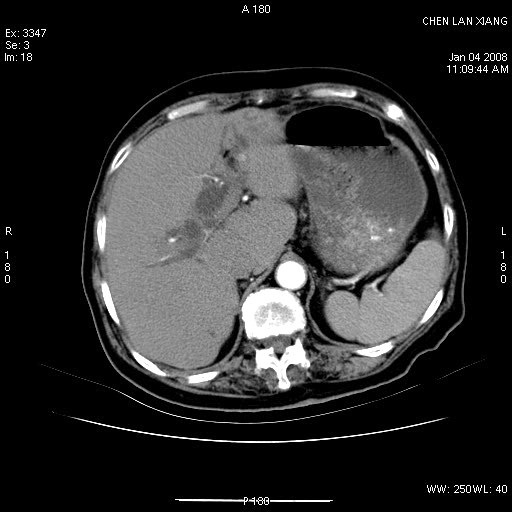

女,76岁,腹痛3-4天,b超示:肝内实性肿物,胆囊强回声,胆总管扩张.

考虑:1、胆总管下端结石伴梗阻性肝内外胆管扩张(肝左叶外侧段肝内胆管多发结石、胆管炎);

2、肿囊癌累及肝,不除外 黄色肉芽肿性胆囊炎。

1 胆总管末端结石伴肝内胆管结石,肝内外胆管扩张。2 胆囊扩大,胆囊壁不规则增厚,内见软组织密度影。考虑:慢性胆囊炎,不除外胆囊癌!

标题: 肝右叶病灶

胆囊癌侵犯肝右叶?

1)胆囊癌伴肝脏转移。2)胆总管下端结石、肝内胆管结石伴肝内外胆管扩张。